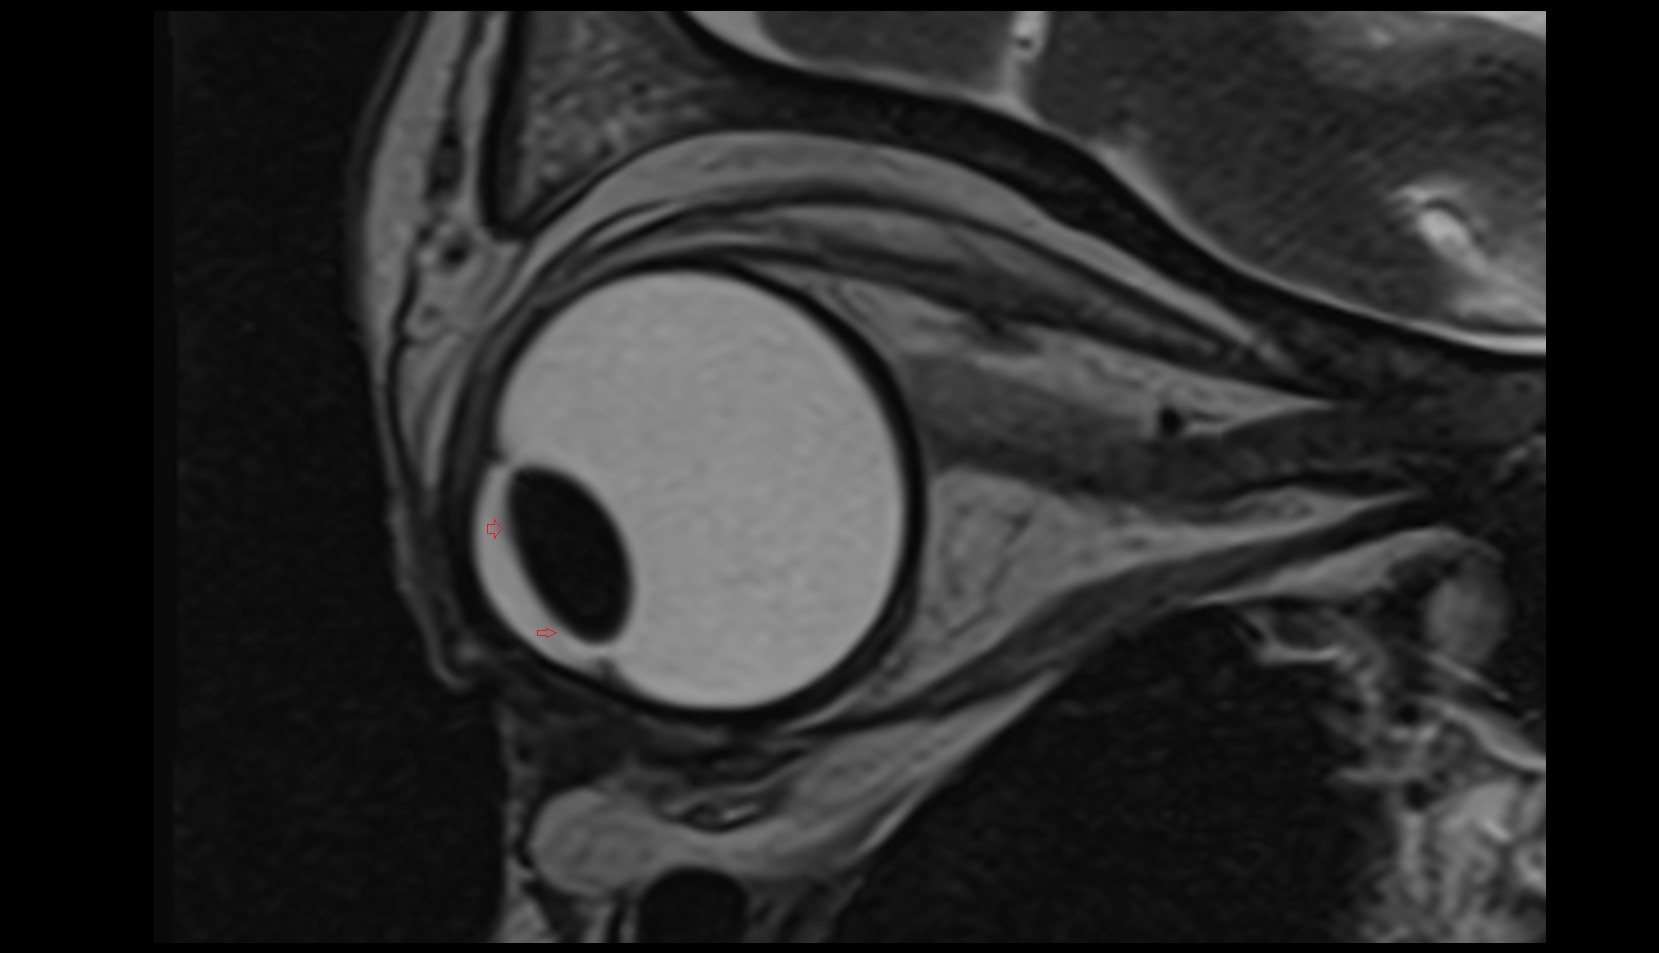

- Head of femur

- Neck of femur

- Hip joint